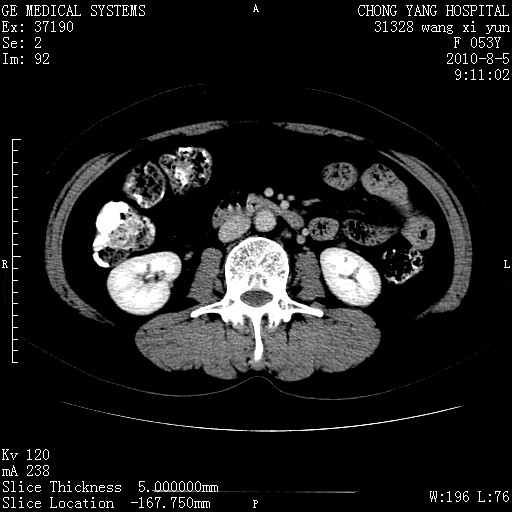

标题: CT28214:F41Y 血尿二十天,建议盆腔平扫加增强。

1)考虑肝左叶胆管细胞癌。2)脂肪肝。

支持胆管细胞ca。